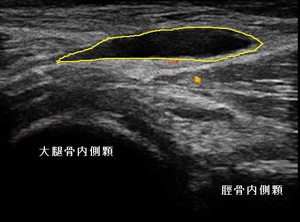

左ひざ裏内側 超音波長軸像 同部 穿針排液18日後

超音波観察を行ったところ、膝窩内側にベーカー嚢腫が認められました。(左上画像の黄色の囲み)

ベーカー嚢腫とは、潤滑油の働きをする膝の関節液を産生する滑液包が、繰り返しの負担や運動、けが、加齢による

関節症、慢性関節リウマチなどが原因で炎症を起こし、ひざ裏に関節液が過剰に貯留する場合を言います。

女性の嚢腫は、かなり大きくなっていましたので、依頼先クリニックで穿針排液してもらうことにしました。約20mlが

吸引されたと報告を頂きました。右上画像は排液18日後ですが、嚢腫が縮小している様子が確認できました。